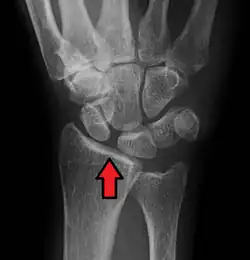

X-ray images indicate scapholunate ligament instability when the scapholunate distance is more than 3 mm, which is called scapholunate dissociation.[7] A static scapholunate instability is generally readily visible, but a dynamic scapholunate instability can only be seen radiographically in certain wrist positions or under certain loading conditions, such as when clenching the wrist, or loading the wrist in ulnar deviation.[6]

Dynamic instability: Increased scapholunate distance (between yellow lines) upon ulnar deviation of the wrist, but not otherwise. -